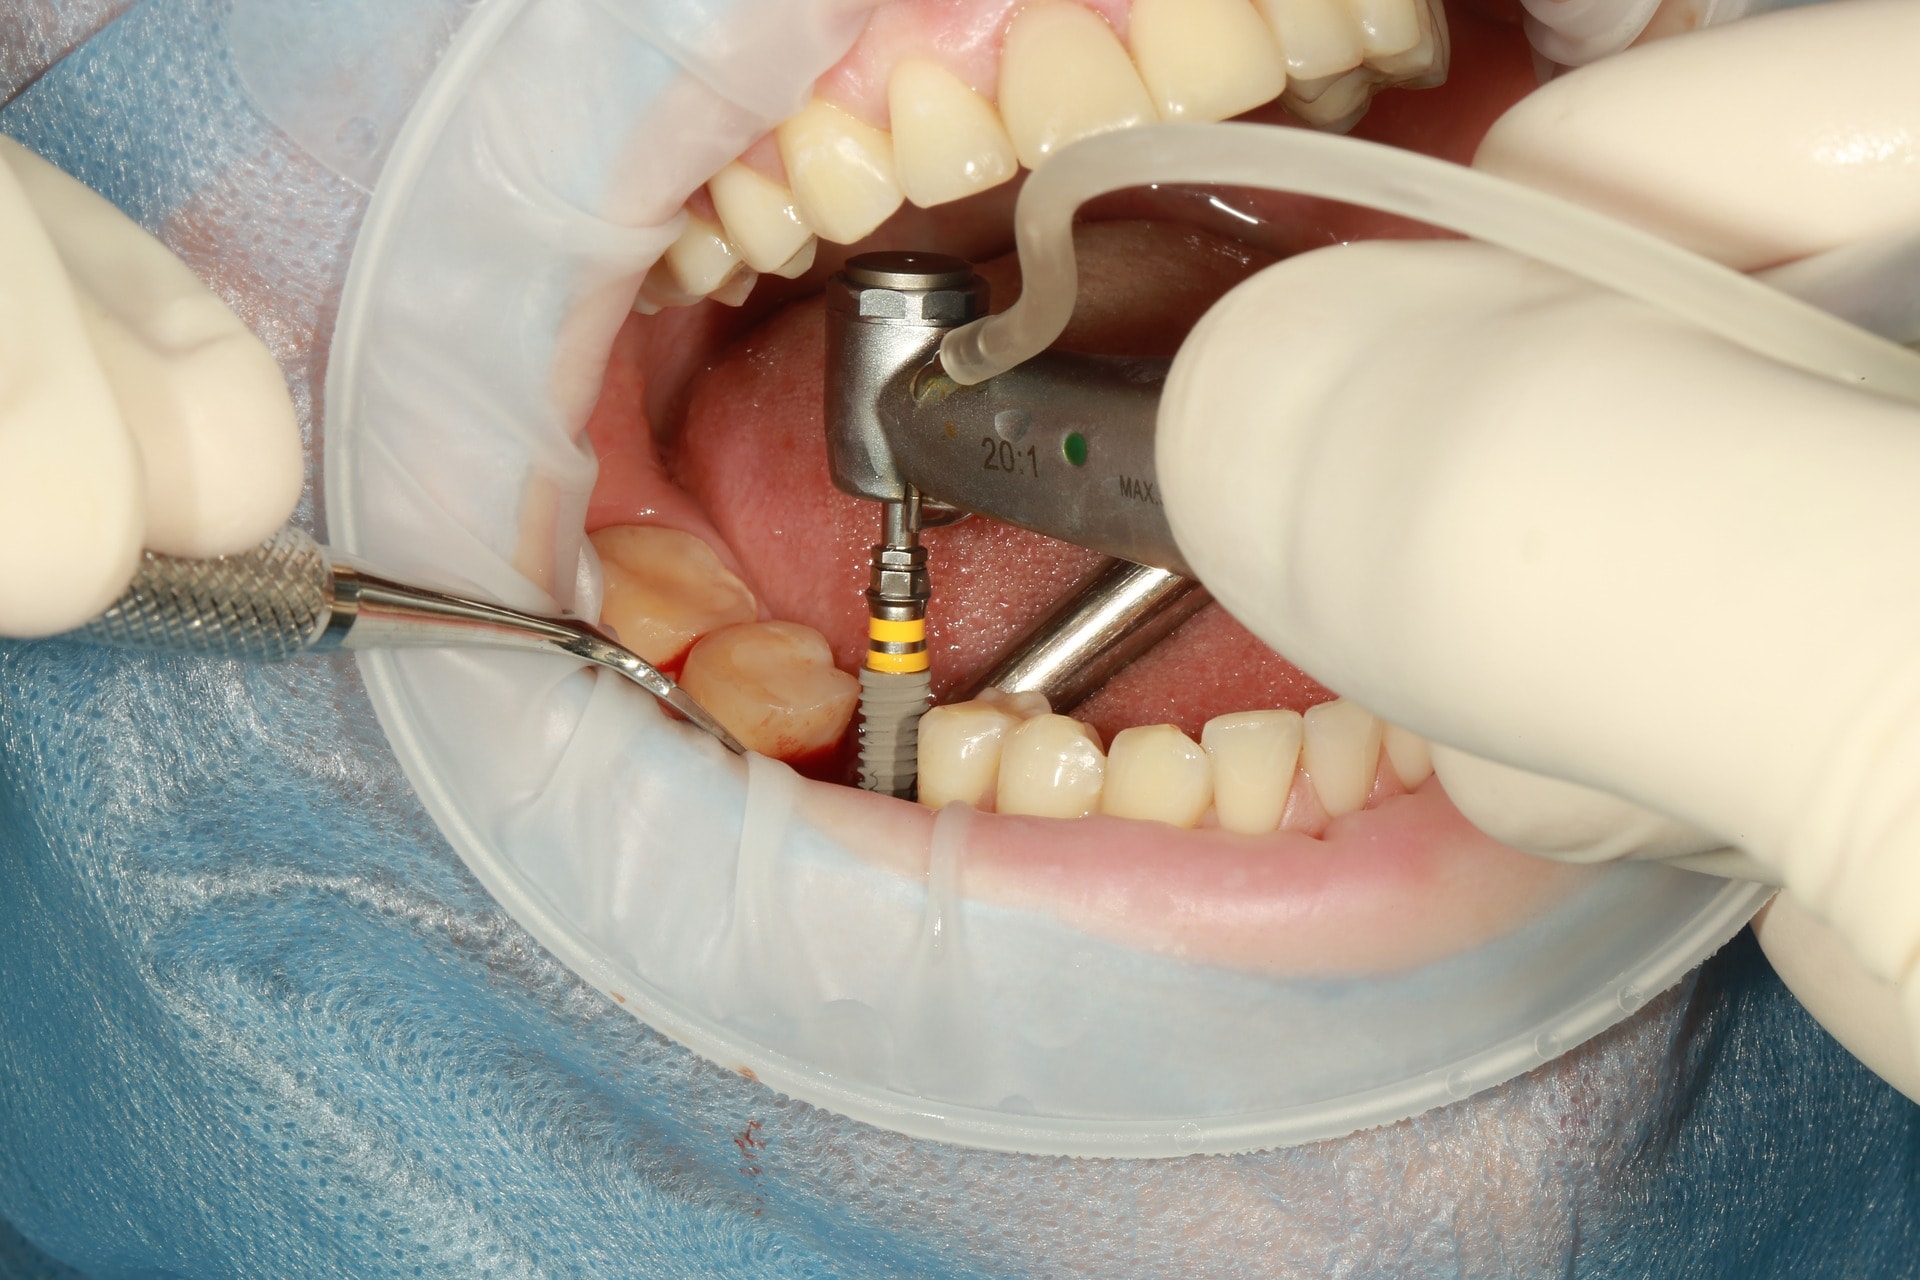

Fogászati implantátum

A fogimplantátum nem más, mint a csontszövetbe ültetett, a környező szövetekkel teljesértékű kapcsolatot létesítő, az emberi szervezet számára befogadható anyagból készülő (biokompatibilis) fogpótlás. Valójában az implantátum csak a természetes fog gyökeréhez hasonlítható, és erre készül el fogtechnikai laboratórium segítségével a természetes fogak koronai részét pótló fogpótlás (korona, hídpótlás stb). Speciális bevonatú titán anyagból készült „műfoggyökerekről” beszélünk, amelyek a csontban tökéletesen rögzülnek, és rájuk fogpótlás készíthető.

Fogszabályozó kezelések segítségével az implantátumok behelyezésének feltételei, ezáltal az implantátumok hosszútávú sikeressége nagyban javítható. Fogszabályozással képesek vagyunk a fogászati implantátumok számára fennálló helyett módosítani, optimalizálni, sőt akár a rendelkezésre álló csontmennyiséget is tudjuk növelni.

Fogszabályozási minilemez

A fogszabályzási minilemez célja hasonló a fogszabályozási miniimplantátumokéhoz. Betonbiztos horgonylati megoldás, mely során a csont felszínén 2-4 minicsavarral rögzítünk egy kisméretű lemezt. A minilemez, mivel sok csavarral rögzül, jóval stabilabb, mint az egyszerű fogszabályozási miniimplantátum. Nagy hátránya, hogy mind a behelyezése, mind az eltávolítása helyi érzéstelenítésben végzett műtéttel zajlik, ami megterhelő lehet pácienseim számára. A műtét kb. hasonlóan zajlik, mint egy fogimplantátum behelyezésénél. A műtét technikai nehézségei miatt ára is sokszorosa a miniimplantátumokénak. Kiválóan végezhető minilemezek segítségével teljes alsó és/vagy felső fogív hátravitel, felső fogív felfelé mozgatása (ínymosoly esetén).